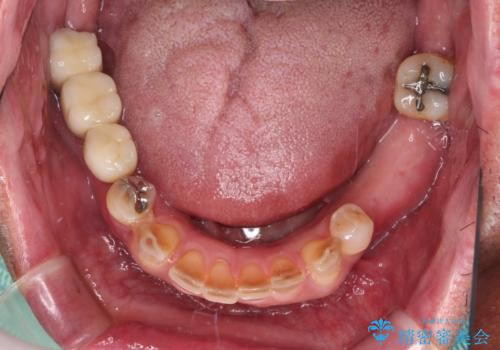

- 奥歯が咬みにくく、前歯がぐらぐらするとのことで来院された患者様です。

咬合力が強く、奥歯が欠損している状態でした。

欠損部はインプラントによる補綴治療を行うこととし、臼歯部が安定した後に、上下前歯部をオールセラミッククラウンにて補綴治療を行うこととしました。